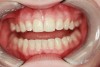

When compared with earlier composites, modern composites shrink less and wear less. In addition, they have more resistance to water and chemical breakdown, better mechanical strength, highly polishability, and better color stability and matching, and are available in various consistencies from flowable to packable.9,10 Composite resins have been combined with other materials to improve caries resistance, as seen with resin ionomers.3 Advancements in bonding technologies, especially the eight generations of dentin bonding, have improved the longevity of restorations and reduced postoperative sensitivity. Resin bonding agents produce an oxygen-inhibited outer layer that remains uncured, therefore the addition of composite materials joins to it.11 Case 1 shows results of modern bonded composites restoring a Class V cavity with no mechanical retention (Figure 1 through Figure 3).

Figure 1  A Class V carious lesion on a lateral incisor.

Figure 1

Figure 2  Preparation following caries removal.

Figure 2

Figure 3  Final Class V restoration using layering technique.

Figure 3